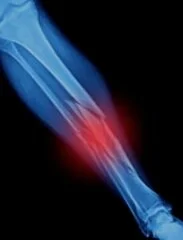

If you have had an accident, injury, or fall, you may have been to an emergency room or urgent care center where X-rays were taken. If you have been told you have a fracture (broken bone), you need to be evaluated by an Orthopaedic Surgeon. Depending on the severity of your fracture, you may need a splint, a cast or even surgery.

Dr. Ialenti treats adult and pediatric fractures. He uses the newest technologies to help you heal and get back to doing the things you love to do. Dr. Ialenti has had extensive experience treating fractures, having trained at the largest and busiest Trauma Center in South Florida, Jackson Memorial Hospital.